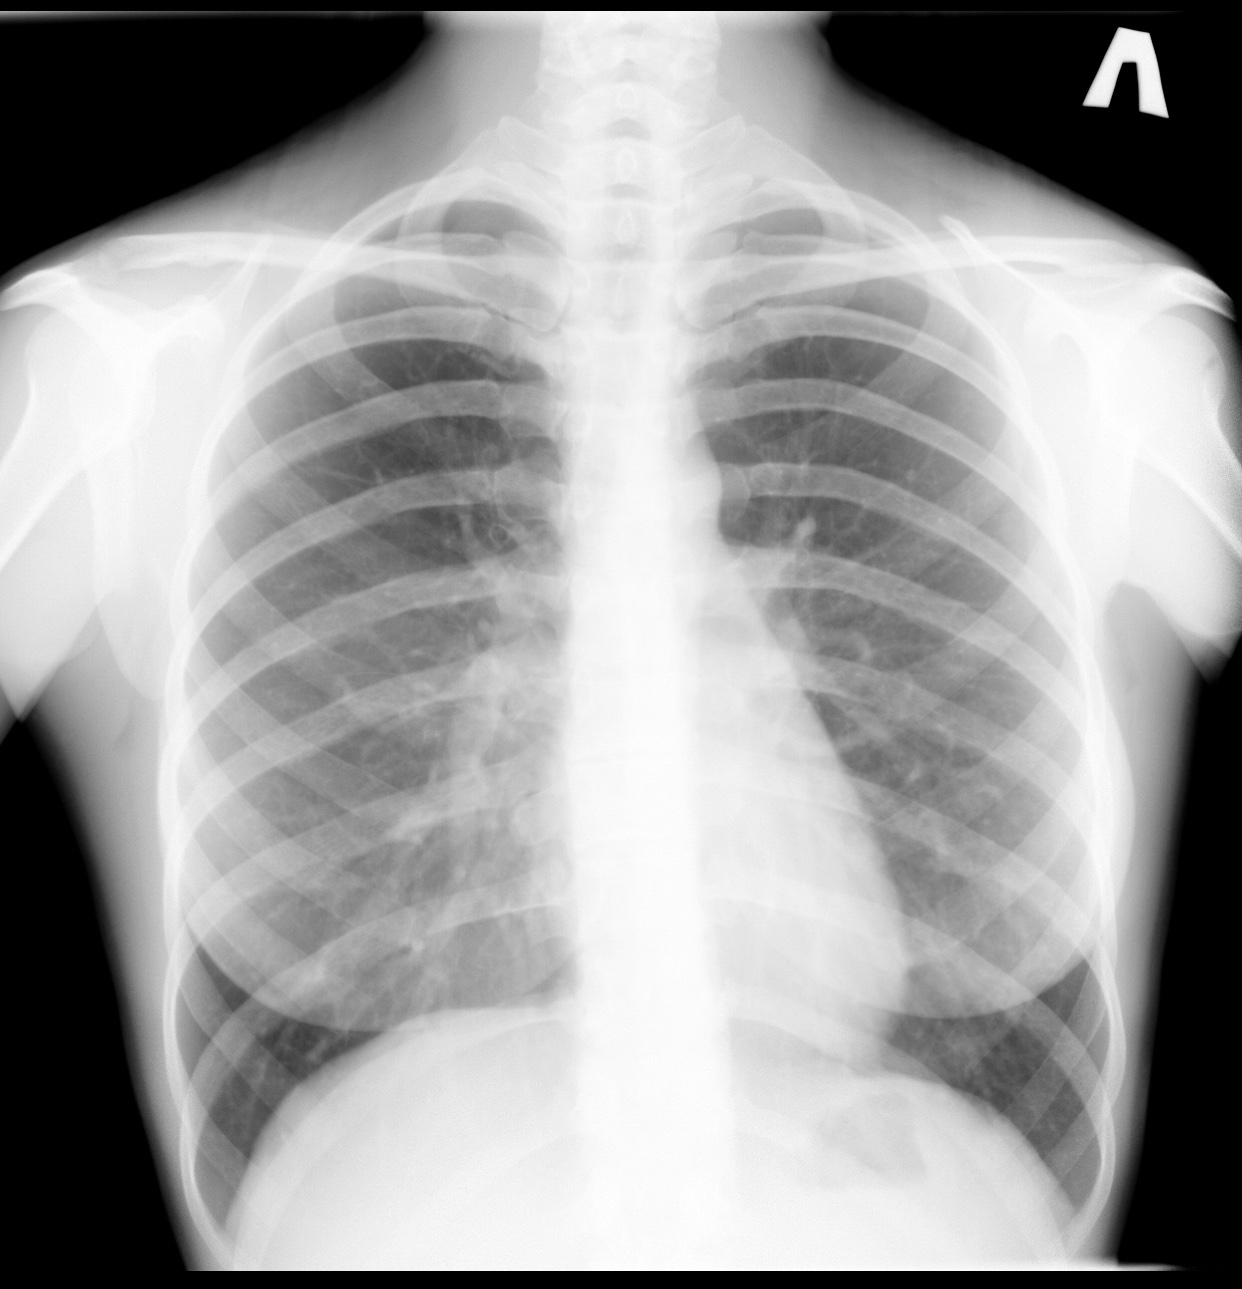

Нормальная рентгенограмма легких: что нужно знать

Раздел: Мудрость в объективе